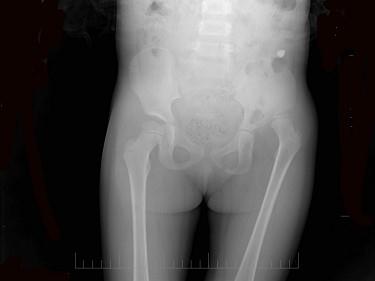

问题 患者女,6岁,左下肢跛行三年,直立时臀部后耸,结合骨盆平片,正确的诊断是?(?)

选项 A.左髋内翻畸形 B.左髋结核 C.左先天性髋关节脱位 D.左股骨头缺血坏死 E.左髋关节炎

答案 C